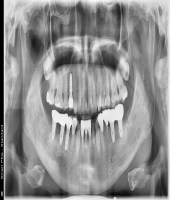

| ● 진료과목 : [임플란트] 틀니 사용중, 임플란트로 교체하기

| ● 내용 : 하악틀니 사용 중 불편감으로 임플란트로 교체한 예 |